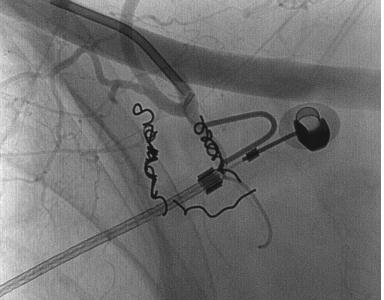

栓塞后弹簧栓子逸出至右肺静脉 |

栓塞后弹簧栓子逸出至右肺静脉 |

弹簧栓子在左心房“狂”跳 |

去哪儿啦? |

在这儿! |

嵌在股深浅动脉分叉处 |

弹簧栓子被移除 |

继续栓塞 |